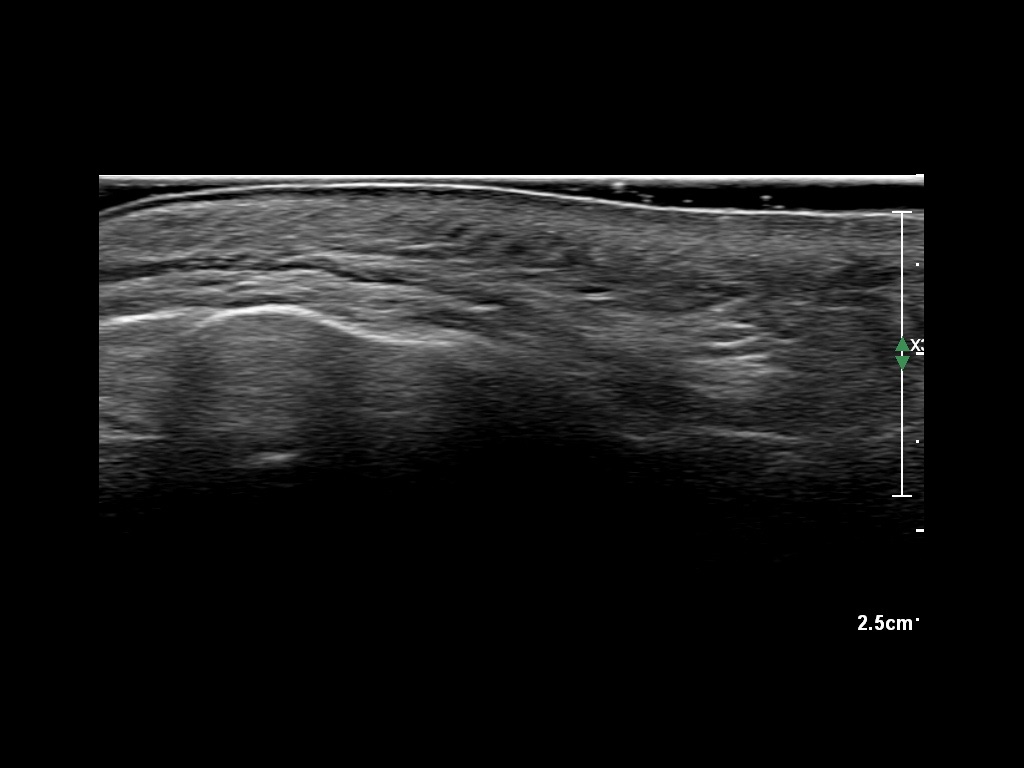

Study the first image to recognize the different layers. If you are sure about the layers, swipe to the second image to view the answer (if applicable).